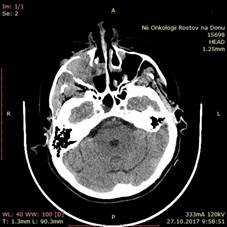

Больная Ж., 1957 года рождения, поступила в отделение ОГШ ФГБУ «РНИОИ» МЗ РФ 10.11.2017 г. с жалобами на затрудненное носовое дыхание через правую половину носа, кровотечения из правой половины носа. Из анамнеза: считает себя больной с ноября 2016 г., когда периодически отмечала кровотечения из правой половины носа. Обращалась к врачу по месту жительства, однако консервативное лечение, проводимое по месту жительства, осталось без эффекта. В марте 2017 г. по поводу зубной боли обратилась к стоматологу, где лечилась по поводу лакунарной кисты. В конце марта 2017 г. возникло кровотечение из правой половины носа. По месту жительства 10.04.2017 г. выполнялось прижигание сосудов слизистой оболочки полости носа справа. 10.05.2017 г. возобновилась кровоточивость с последующим носовым кровотечением. В ГБУ РО РОКБ 06.07.2017 г. выполнена операция: правосторонняя гайморотомия, этмоидотомия, удаление новообразования правой половины носа с использованием видеоэндоскопических технологий. Послеоперационный гистологический анализ № 57554-61 – кавернозная гемангиома. Больная была выписана в удовлетворительном состоянии с восстановленным носовым дыханием, кровотечение из правой половины носа прекратились. Через 1 неделю возобновились носовые кровотечения из правой половины носа, была направлена в ЛОР-отделение ГБУ РОКБ, где 18.08.2017 г. выполнена операция – правосторонняя гайморотомия комбинированным доступом (ревизия по Дэнкеру) с использованием видеоэндоскопических технологий, обезболивание общее. Послеоперационный гистологический анализ № 70827-30 от 25.08.2017 г. (ИГХ) меланома. Наблюдалась по месту жительства. Однако носовые кровотечения не прекратились, что побудило больную обратиться в ФГБУ «РНИОИ» МЗ РФ, где были пересмотрены гистологические препараты. Выполнены СРКТ околоносовых пазух и МРТ сосудов головного мозга. При осмотре специалиста в профильном кабинете клинико-диагностического отделения ФГБУ «РНИОИ» МЗ РФ: лимфатические узлы шеи не пальпируются. Лицо асимметричное за счет распространения опухоли в мягкие ткани правой щеки. Пальпаторно – костные края орбиты не изменены. При орофарингоскопии – открывание полости рта в полном объеме. При передней риноскопии – в общем носовом ходе справа гнойно-геморрагические корки, опухоль не определяется при осмотре. СРКТ от 27.10.2017 г. – опухоль правой верхнечелюстной пазухи 3,8х3,9х3,3 см с разрушением ее передней, задней стенок, распространением в мягкие ткани щеки и правый общий носовой ход; легочная ткань без очагов; патологических объемных образований в брюшной полости и полости малого таза не выявлено (рис. 3).

Рис. 3. СРКТ придаточных пазух носа: справа – опухоль правой верхнечелюстной пазухи 3,8х3,9х3,3 см с разрушением ее передней, задней стенок, распространением в мягкие ткани щеки и правый общий носовой ход